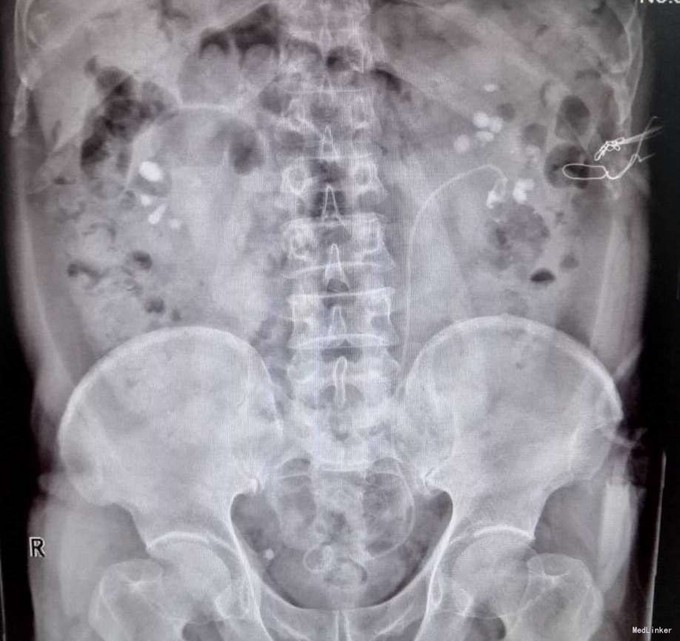

3、查体:未见明显阳性体征 4、辅助检查:外院平片:双肾多发结石;我院CTU:双肾多发结石,左侧肾盂输尿管连接处结石,并双肾积水,左肾明显,双侧肾盂、输尿管炎症。

5、诊断:肾结石(双肾多发结石) 6、治疗:入院后完善相关检查,双肾CTU:双肾多发结石,左侧肾盂输尿管连接处结石,并双肾积水,左肾明显,双侧肾盂、输尿管炎症。排除手术禁忌症后行左侧PCNL术,术后恢复良好,拔出肾造瘘管后,先出院休息,2周后返院进一步治疗